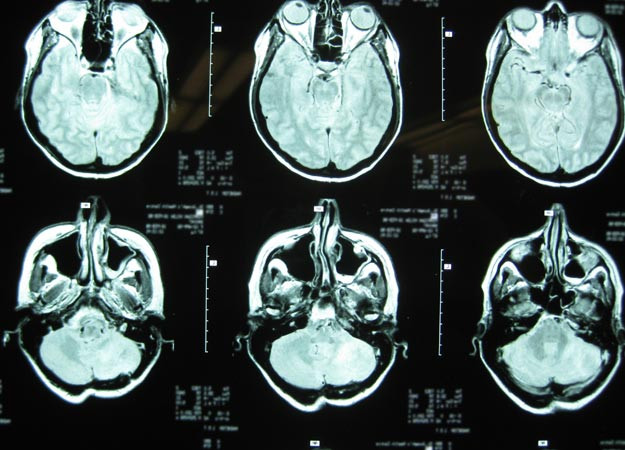

RMN-urile facute in timp ce subiectii purtau "casca lui Dumnezeu" arata o activitate crescuta in zona creierului care primea semnale electromagnetice.